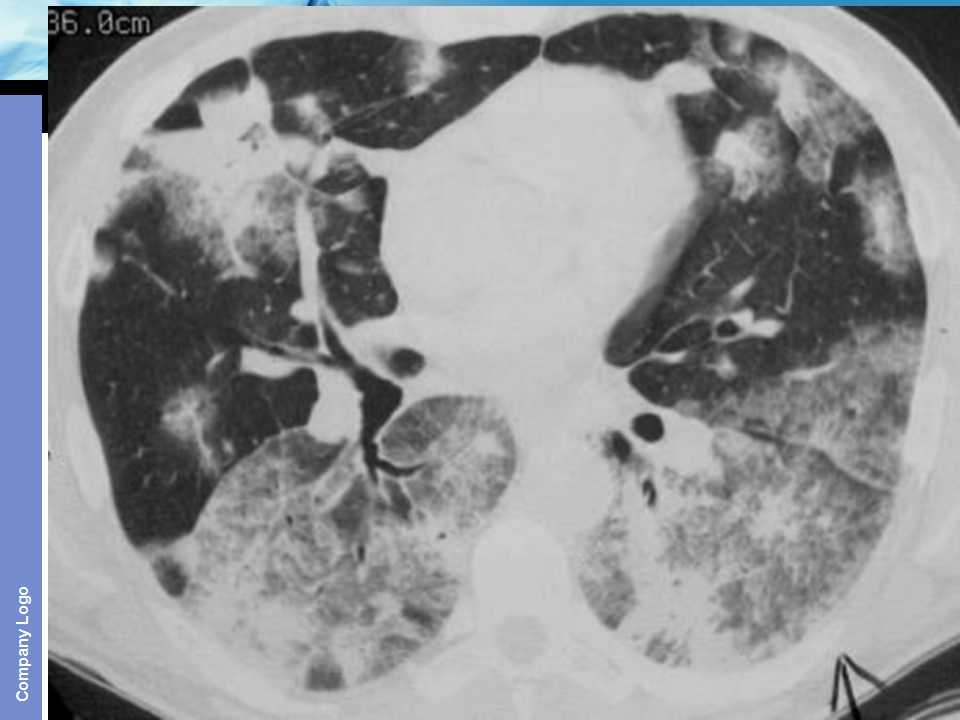

肺癌影像诊断